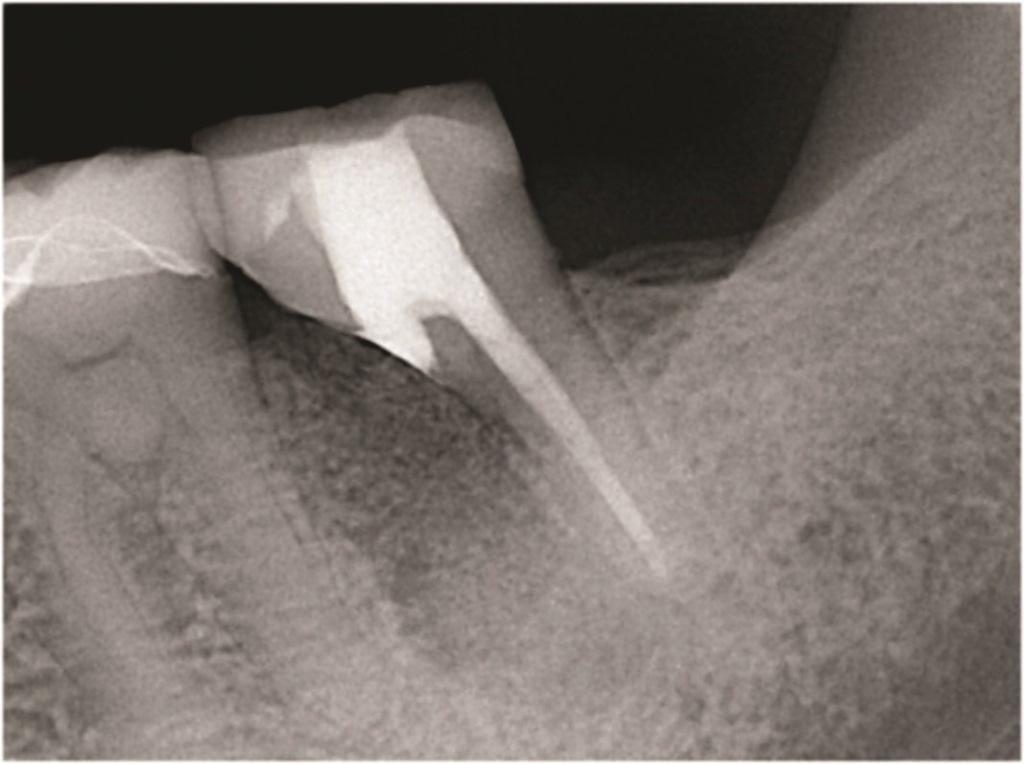

К таким патологическим состояниям относятся вертикальные переломы корней, перфорации корней, пародонтит с поражением корней из-за проблем в области фуркации или сближения корней, сочетанные эндодонтическо-пародонтальные дефекты на фоне коротких корней, устойчивые фуркационные дефекты, значительные не поддающиеся лечению внешние резорбтивные дефекты и другие (Фото 1–4). Когда подобные состояния затрагивают однокорневые зубы, удаление часто является единственным способом устранения патологии. Однако в случае многокорневых зубов существует дополнительная возможность: полное удаление источника патологии с одновременным сохранением функциональности зуба, что демонстрирует опубликованные показатели выживаемости на уровне 80–90%. При правильном выполнении с учетом описанных в статье факторов такое функциональное состояние может сохраняться в долгосрочной перспективе со средним сроком службы от 6 до 20 лет.

Фото 2: Зуб 4.6 с ранее проведенным апикальным хирургическим вмешательством, показывающий потерю кости вокруг переломанного мезиального корня.